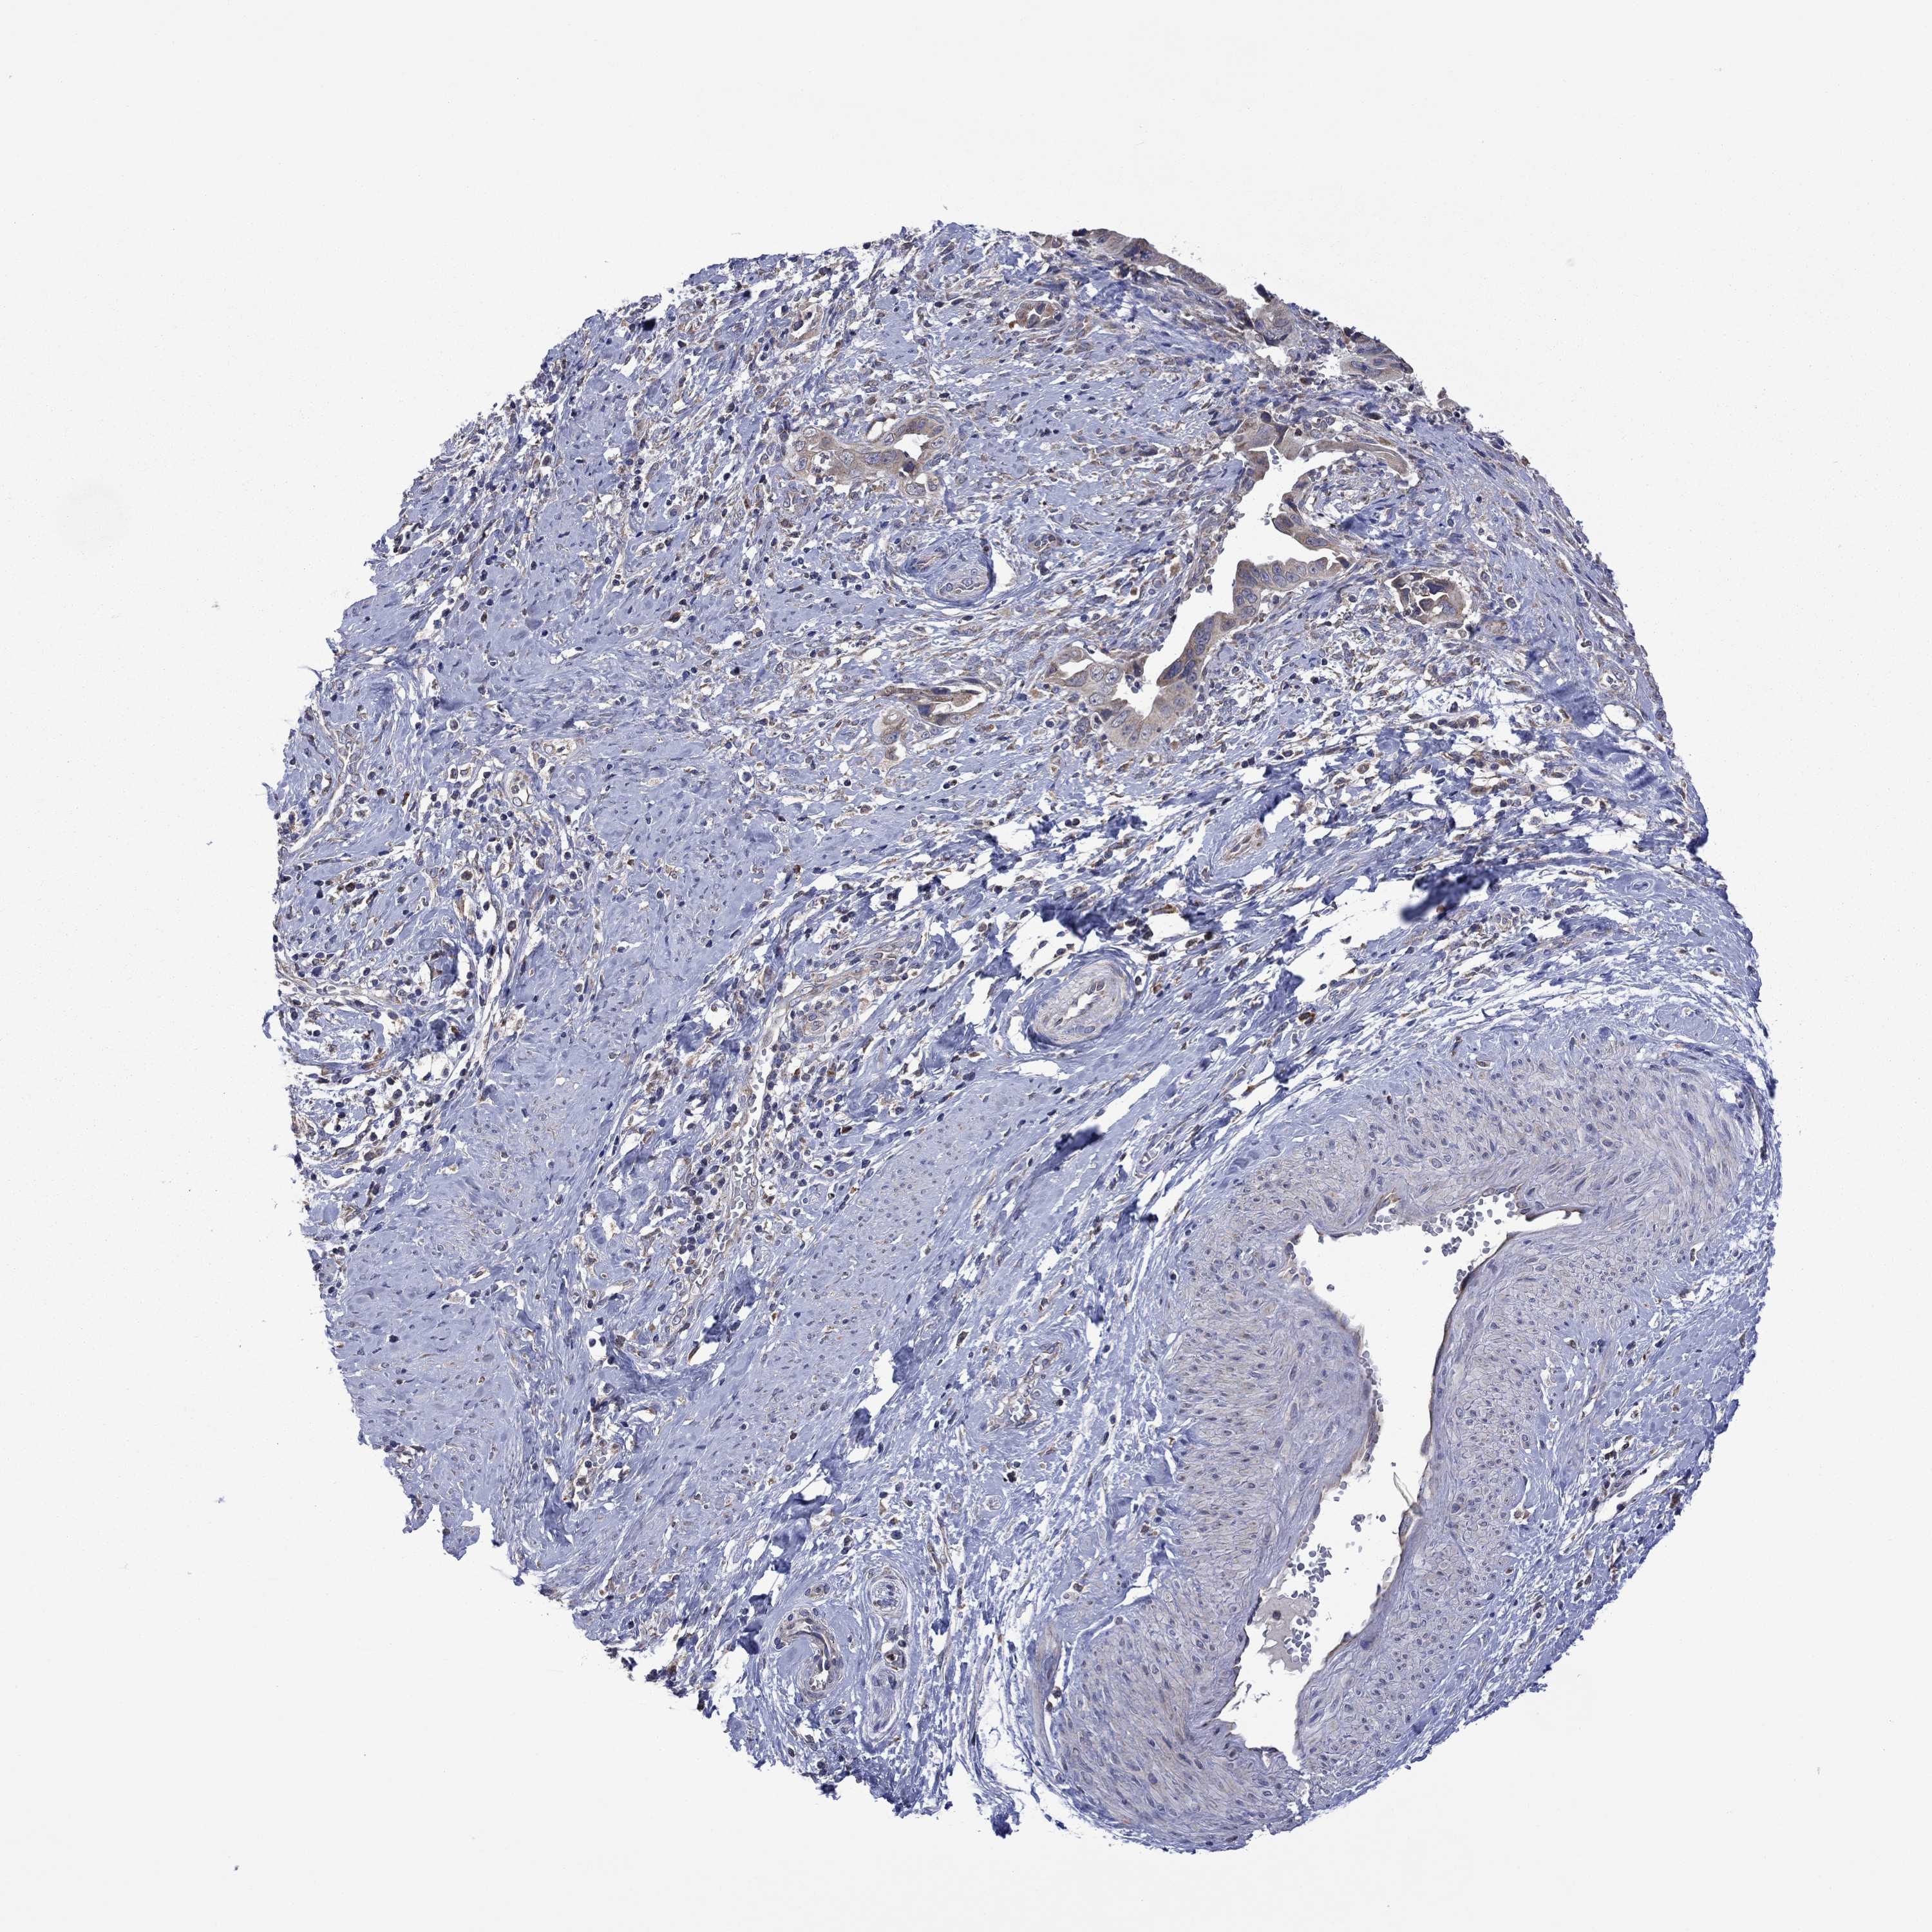

CERVICAL CANCER - Protein expressioni

A mouse-over function shows sample information and annotation data. Click on an image to view it in a full screen mode. Samples can be filtered based on level of antibody staining by selecting one or several of the following categories: high, medium, low and not detected. The assay and annotation is described here.

Note that samples used for immunohistochemistry by the Human Protein Atlas do not correspond to samples in the TCGA dataset.

Antibody stainingi

Antibody staining in the annotated cell types in the current human tissue is reported as not detected, low, medium, or high, based on conventional immunohistochemistry profiling in selected tissues. This score is based on the combination of the staining intensity and fraction of stained cells.

Each image is clickable and will lead to virtual microscopy that enables deeper exploration of all samples and also displays staining intensity scores, fraction scores and subcellular localization as well as patient and tissue information for each sample.

Antibody HPA067869

Squamous cell carcinoma, NOS